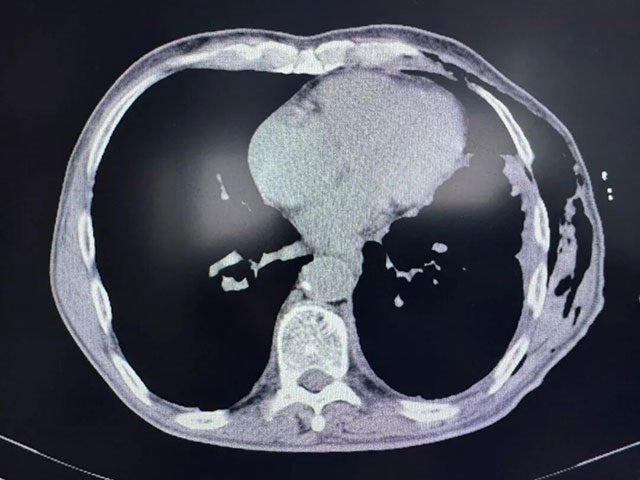

術(shù)前胸部CT

術(shù)后胸部CT